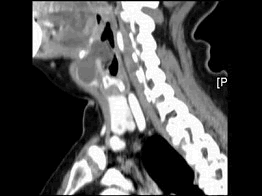

女,57岁,颈部不适,CT如图所示,应诊断为()

[单选题]女,57岁,颈部不适,CT如图所示,最可能的诊断是()A.咽囊囊肿B.鳃裂囊肿C.甲状舌管囊肿D.颈部淋巴管瘤E.颈部神经鞘瘤

[单选题]女,57岁,颈部不适,CT如图所示,最可能的诊断是( )。A.咽囊囊肿B.鳃裂囊肿C.甲状舌管囊肿D.颈部淋巴管瘤E.颈部神经鞘瘤